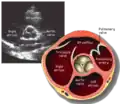

Apical four chamber (A4C)

This view is obtained at the apex of the heart and looking toward the base of the heart (where the valves are). In this view, the mitral valve, tricuspid valve, and all four chambers are visible. This view shows the right ventricle from base to apex and is a useful view to estimate RV systolic function. TAPSE (= tricuspid annular plane systolic excursion) is also measured in this view with M-mode through the lateral tricuspid annulus.

Structures:

- Inferior septum and anterior lateral segments of the left ventricle

- Right ventricle

- Left atrium

- Right atrium

- Mitral valve

- Tricuspid valve

Measurements in this view can be used to quantify the heart:

- RV size and function; TAPSE

- Left atrial size

- Right atrial size

- Mitral valve flow is best seen in this view and has the best angle with probe to estimate flows

- Tricuspid valve flow

- Tissue doppler at the mitral valve annulus (septum and lateral wall) for diastolic function

- Agitated saline bubble study for right to left shunting (PFO, ASD, VSD)

- With contrast, apical and mural LV thrombi can be easily seen